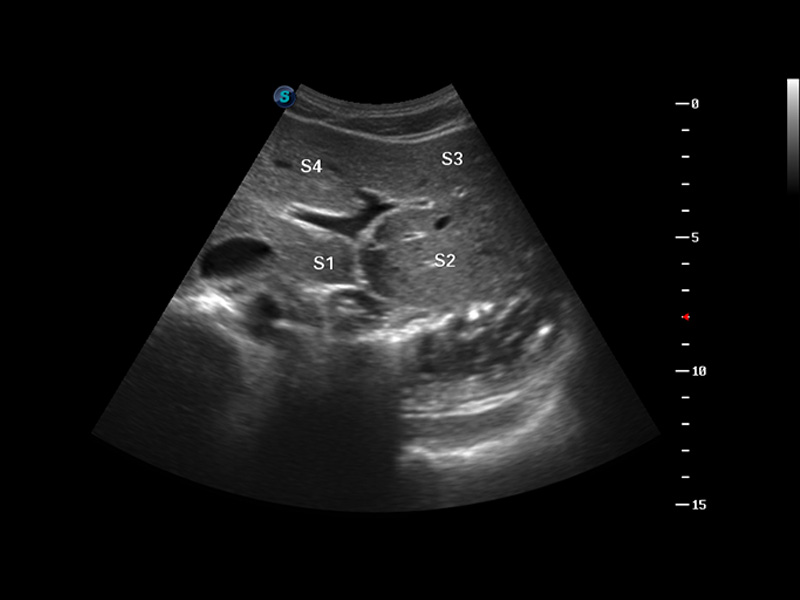

S8 EXP便携式彩色多普勒超声诊断仪是九州酷游研发的高端全身应用型便携彩超。高通道的VIS平台融合可视化(Visual)、智能化(Intelligent)和人性化(Smart)的特点,配以九州酷游自主研发生产的探头大家族,使您能够快速、准确的获得病人信息,提高工作效率的同时减轻疲劳。

μ-Scan微米成像